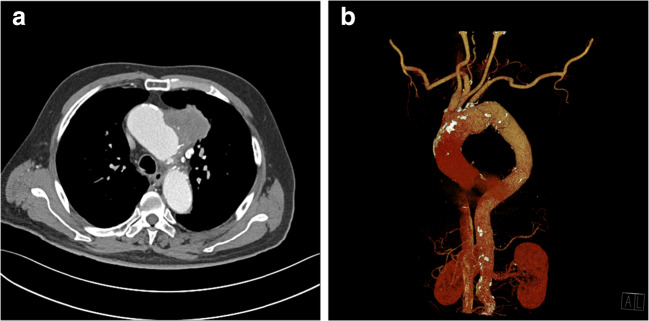

An 81-year-old man was referred for evaluation of a mediastinal mass. He visited the emergency department presenting with hemoptysis, and the mass was revealed subsequently on chest computed tomography (CT). He complained of no pain but suffered respiratory symptoms including cough and sputum. He had a history of colon cancer 7 years previously, and had been on hypertension medication for 10 years. The mass was located in the left upper thorax, with a long diameter of approximately 5.8 cm, exhibiting poor enhancement on chest CT (Fig. 1a). There was no evidence of either aortic dissection or significant steno-occlusive lesion on reconstructed CT angiography (CTA) (Fig. 1b). The clinician suspected malignancy in the mediastinum, such as a thymic carcinoma, or possible primary lung cancer and metastasis.

Fig. 1.

a Computed tomography (CT) revealed a mediastinal mass in the left upper thorax. The mass diameter was approximately 5.8 cm, and it displayed poor enhancement. b There was no evidence of aortic dissection or significant steno-occlusive lesion on reconstructed CT angiography (CTA)